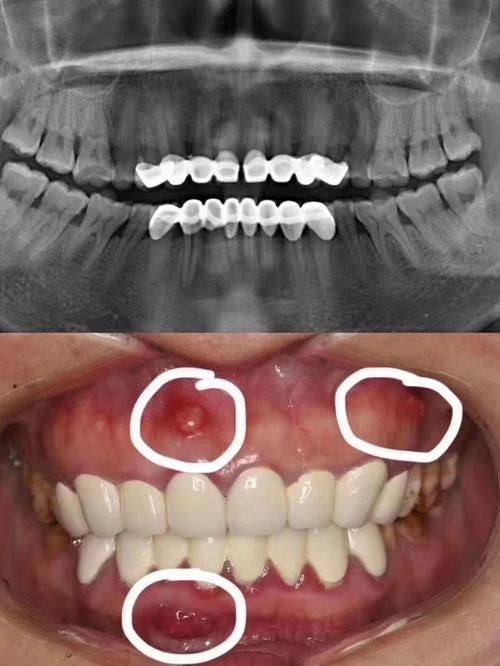

虽然烤瓷牙有特别多优点,但也存在一些不足之处。其中一个问题是美观可能会受影响。因为烤瓷牙的金属基底,可能会导致牙龈边缘透出灰线,尤其是在笑起来或者张嘴的时候,就会比较明显,这对于一些对美观要求较高的患者来说,可能就不太能接受。

部分患者还可能面临过敏风险。有些患者对金属过敏,在安装烤瓷牙后,可能会出现牙龈红肿的情况,不仅影响美观,还会让口腔产生不适感。